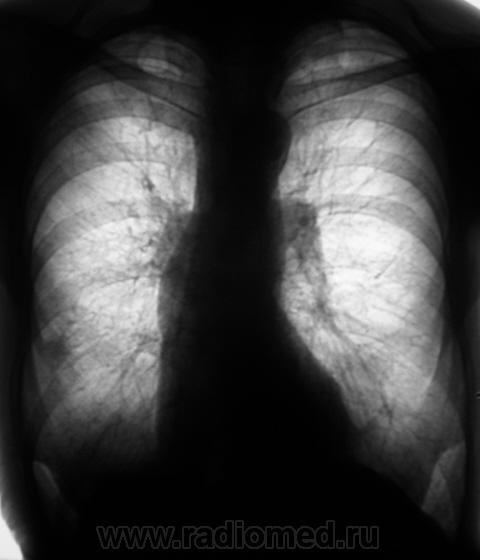

Ваше мнение.   Динамика есть или динамики нет?

Динамика отрицательная.

Дмитрий